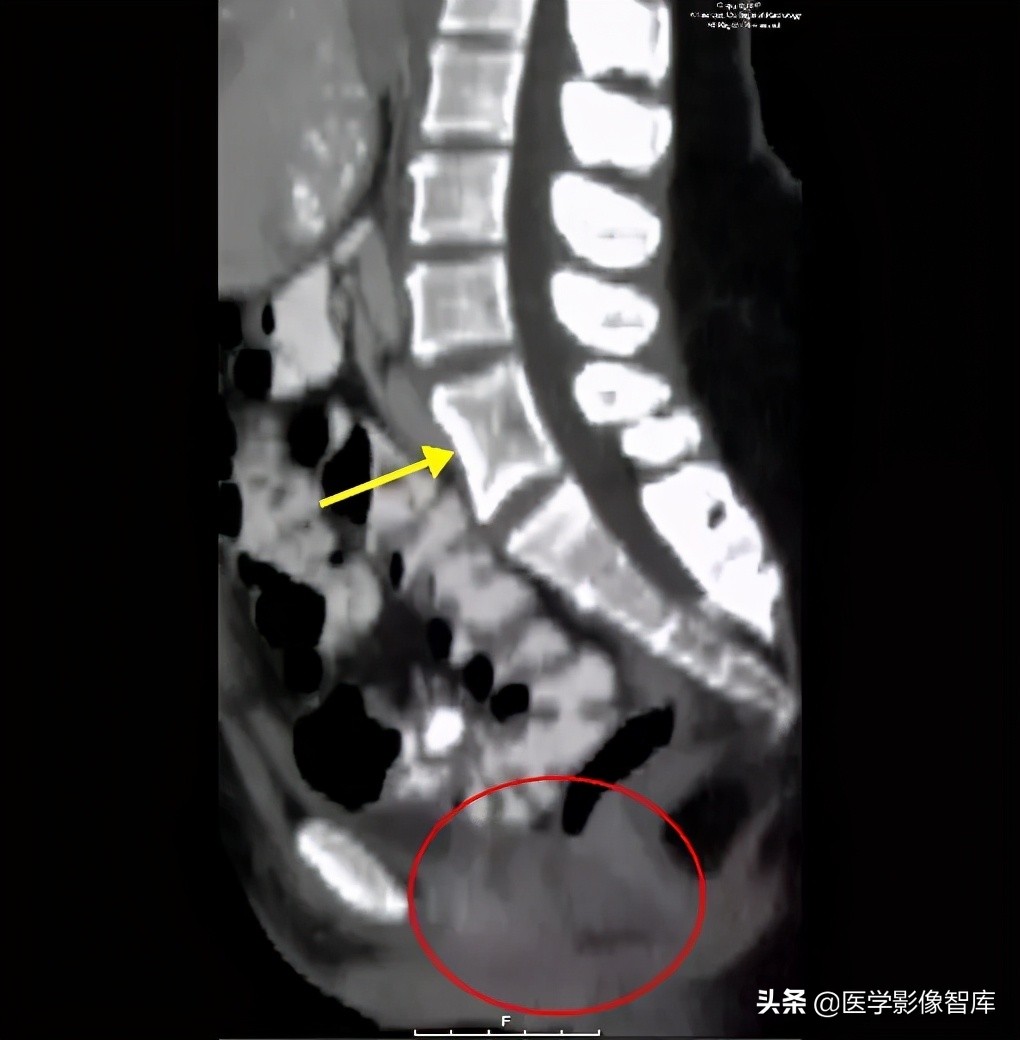

图 2. 矢状位 CT 显示椎体融合(黄色箭头)和阴道发育不全、子宫缺如(红色圆圈)